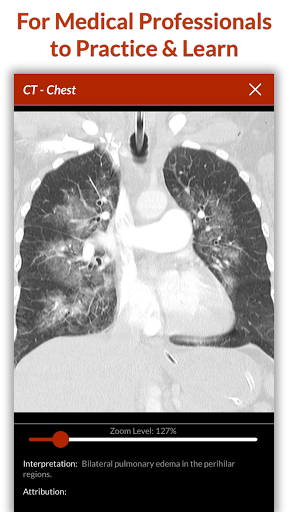

• 200+ thư viện trường hợp được biên soạn và đánh giá bởi các bác sĩ lâm sàng chuyên gia

• Hơn 30 chuyên khoa chẩn đoán, bao gồm Y học cấp cứu, Sản phụ khoa và Nhi khoa

Được tạo ra bởi các nhà giáo dục y khoa từ một số bệnh viện hàng đầu tại Hoa Kỳ và được các chuyên gia y khoa được cấp phép đánh giá ngang hàng, các mô phỏng của chúng tôi được thiết kế theo các phương pháp thực hành y khoa tốt nhất theo tiêu chuẩn của ngành, đặt ra tiêu chuẩn cao cho sinh viên y khoa và các chuyên gia trên toàn thế giới.